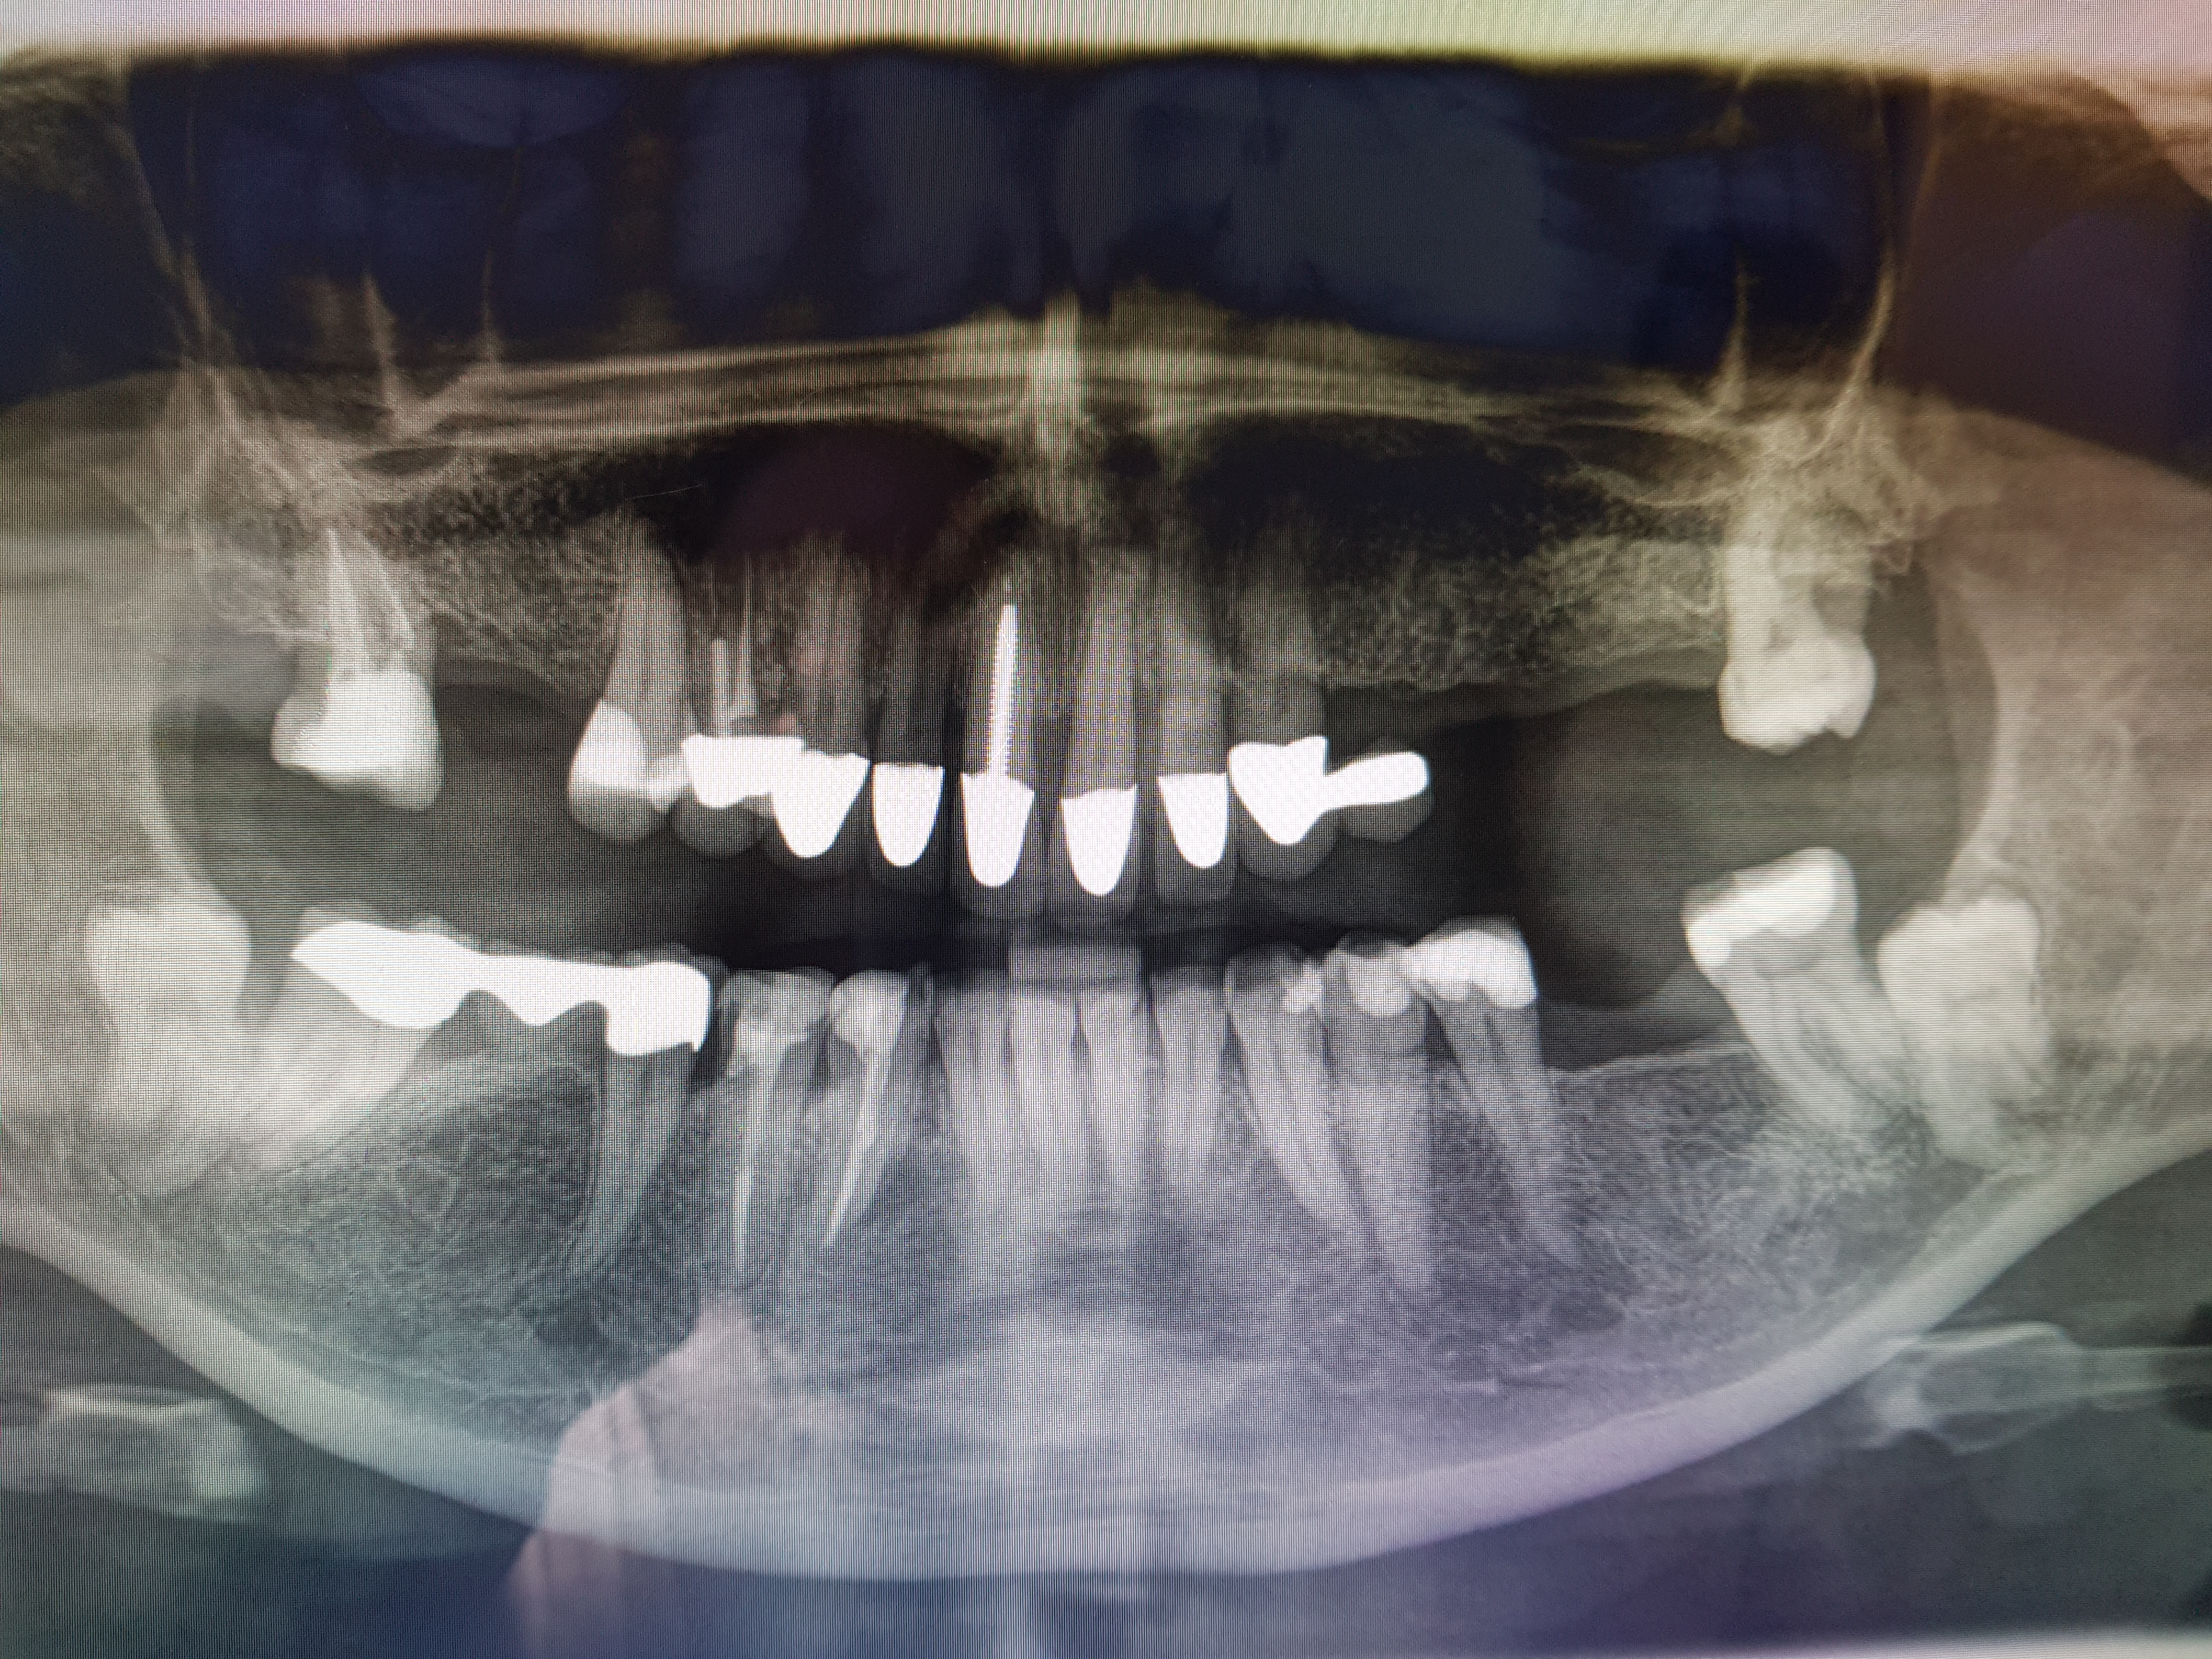

2 Implantate setzen und Zahnersatz im Ober- und Unterkiefer

17-23 Zirkon-BrĂŒcke, 24-26 Supra-BrĂŒcke, OK, UK Gesamtplanung auf 3 PlĂ€nen, aus therapeutischen GrĂŒnden getrennt